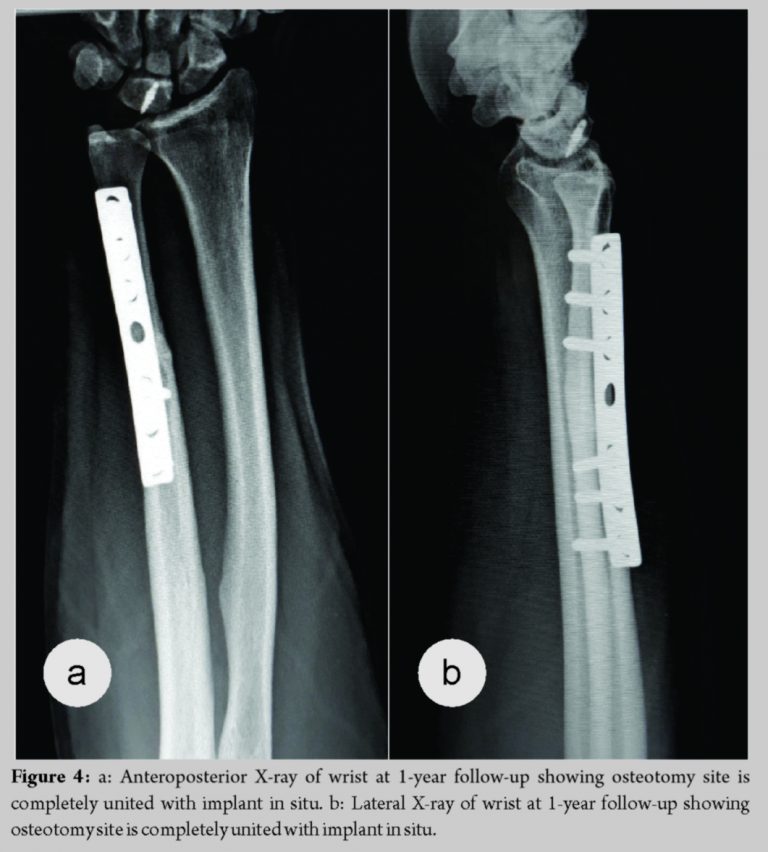

A 30-year-old male complains of the right wrist pain for 6 months due to fall on an outstretched hand. The patient was treated with below elbow cast for 6 weeks. Since then, the patient had wrist pain around ulnar the head by clicking on pronation, palmar flexion, and ulnar deviation. Range of motion was painful after 70° of palmar flexion, 10° of ulnar deviation with pronation. The scaphoid shift test and fovea sign test were negative whereas ulnocarpal stress test was positive. Anteroposterior view of wrist X-ray showed positive ulnar variance >2 mm, whereas the lateral view showed normal findings (Fig. 1). Magnetic resonance imaging (MRI) revealed dorsal scapholunate ligament tear with hyperintensity changes of ulnotriquetral ligament and ulnar side of the triquetrum (Fig. 2). Pre-operative disabilities of the arm, shoulder, and hand (DASH) score was 40.4 and visual analog score (VAS) score was 7. The patient was planned for modified Brunelli technique proposed by Elsaftawy et al. in which reconstruction of the scapholunate ligament with transfer of partial flexor carpi radialis tendon (Fig. 3) from plantar to the dorsal side through the distal pole of scaphoid and is anchored to the lunate with a specialized suture anchor, and extra-articular ulnar shortening osteotomy for positive ulnar variance in one setting. The patient was kept in below elbow dorsal slab for 6 weeks. After 6 weeks, wrist range of motion was gradually started. Heavy work started after 3 months. The patient had full range of motion at 6 months with DASH score of 10 and VAS score of 1 with complete radiological union at 1-year follow-up (Fig. 4).

The ulnar impaction syndrome is yet another cause of wrist pain that can cause considerable disability. The most common procedures used to address ulnar impaction syndrome are ulnar shortening osteotomy, open or arthroscopic distal wafer resection with or without triangular fibrocartilage complex debridement. Advantages of an ulnar shortening osteotomy include unloading the ulnar carpus, precise shortening, tightening the ulnocarpal ligament complex, and avoiding damage to the distal articular surface of the ulna [10]. Woitzik et al. [8] in his case series described that positive ulnar variance more than 2 mm, extra-articular diaphyseal ulnar shortening osteotomy is the best choice and when ulnar variance <2 mm with central or peripheral perforation of triangular fibrocartilage complex arthroscopic wafer surgery is the treatment of choice. We presented a case of 30-year-old male who presented with complaints of wrist pain with significant restriction to carry out daily activities. Initial radiographs were essentially normal, and hence, scapholunate dissociation with ulnar impaction syndrome was missed initially and was diagnosed with dynamic imaging and MRI. The patient was managed with modified Brunelli technique proposed by Elsaftawy et al. in 2014 and extra-articular ulnar diaphyseal shortening step cut osteotomy as described above in one setting. The patient improved significantly over 3 months postoperatively with the DASH improving significantly from 40 to 10 over 6 months and VAS scores from 7 to 1. Now, post-operative 1 year, the patient is symptom free and full range of motion with the radiological union at ulnar shortening osteotomy site.